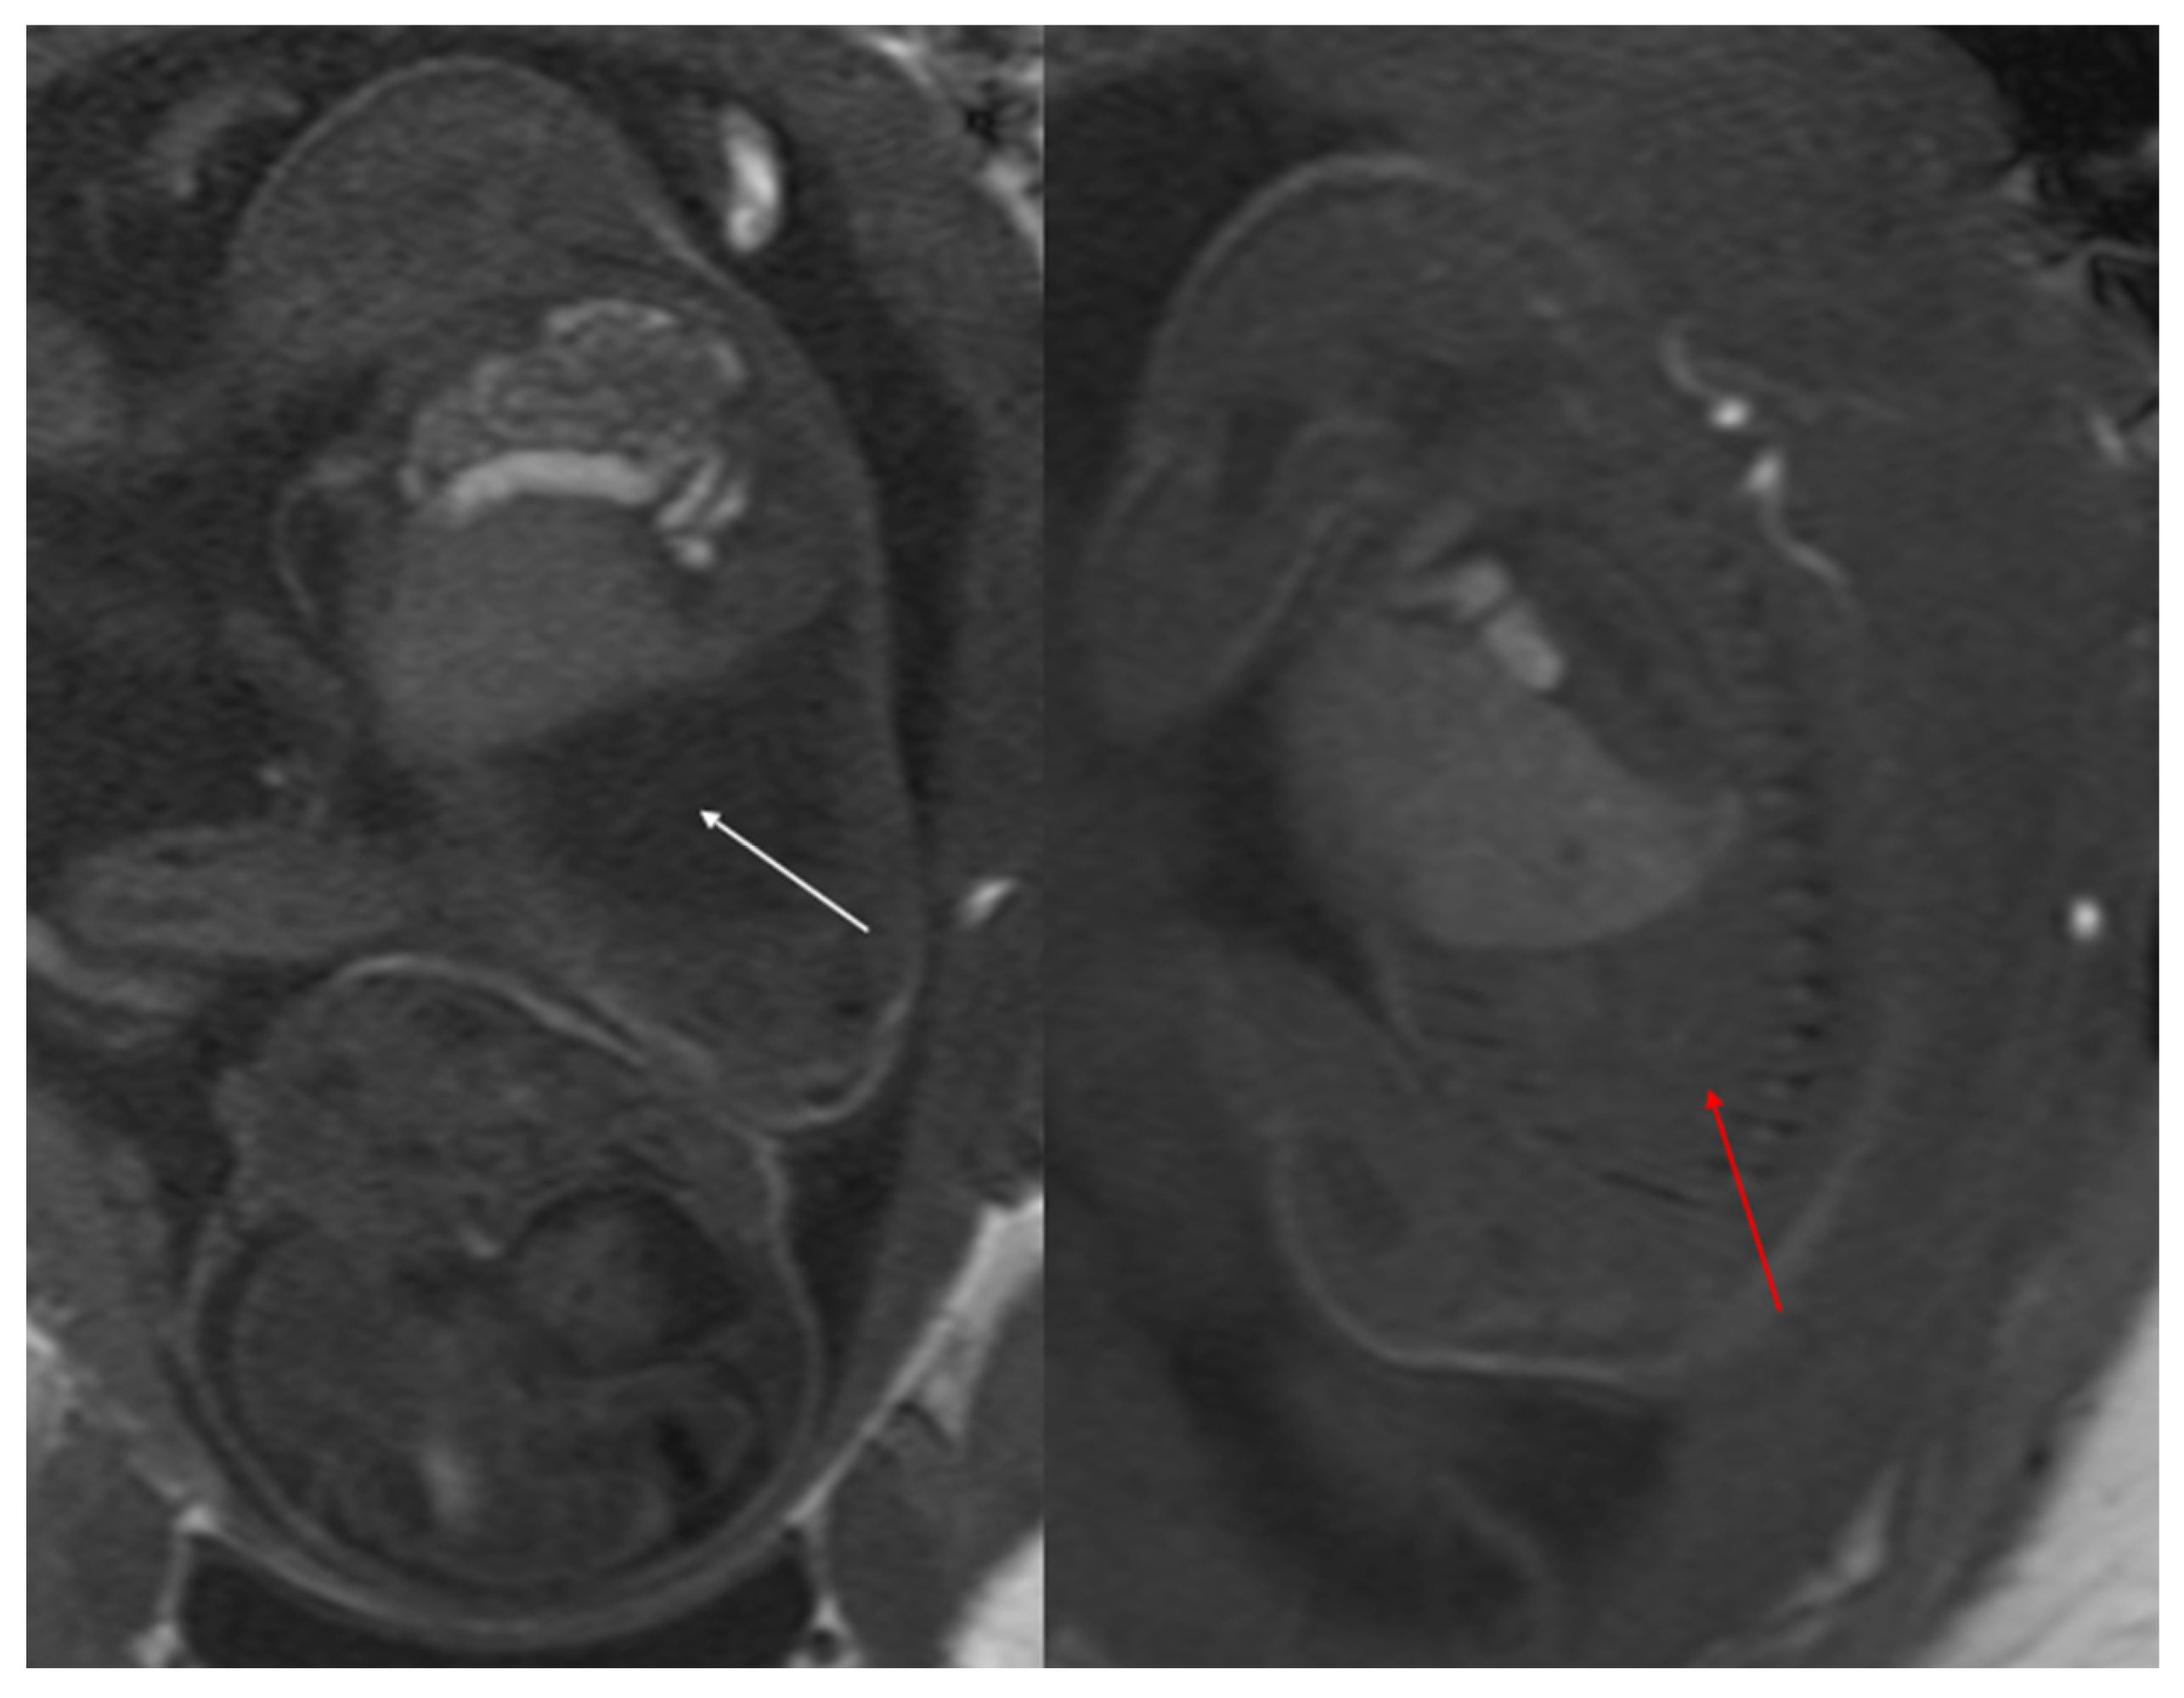

Figure 3. CPAM type III. Coronal T2 HASTE image shows, diffuse hyperintensity of the entire left lung (white arrow), without evidence of recognizable cystic structures. Note the normal intensity of the right lung (red arrow).

Congenital pulmonary airway malformations (CPAM) are subdivided into five types (0–4), with each type characterized by distinct features: Type 0 involves the trachea and mainstem bronchi and is lethal postnatally; Type I affects the bronchi and proximal bronchioles and is associated with large cysts (Figure 1); Type II involves the bronchiolar area with smaller cysts (less than 2 cm) (Figure 2); Type III affects the bronchiolar/alveolar duct region, often appearing as homogeneous hypodense masses on CT (Figure 3); and Type IV involves the alveolar/saccular region, causing unlined cysts [8].